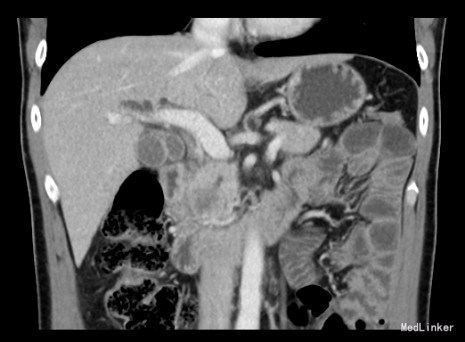

查体:身目重度黄染,上腹部轻压痛; 辅助检查: 白细胞WBC:10.96; 血红蛋白Hb:145g/L;血小板PLT:241x10^9/L 丙氨酸氨基转移酶ALT 357 U/L ;天冬氨酸氨基转移酶AST 191 U/L;白蛋白ALB 40.9 g/L ;总胆红素TBIL 151.2 umol/L;直接胆红素DBIL 85.8 umol/L 肿瘤标记物: 甲胎蛋白(AFP) 5.00 ug/L 0.00 - 20.00 ;癌胚抗原(CEA) 9.19 ug/L ↑ 0.00 - 5.00 ;CA125 71.00 U/mL ↑ 0.00 - 35.00 鳞癌抗原(SCC) 0.90 ug/L 0.00 - 1.50 ;CA19-9 〉12000.00 U/mL CT:平扫胰体尾部萎缩,胰头区不规则肿大,局部可见类圆形软组织肿块影,大小约44×43mm,边界模糊,内部密度不均,其内可见斑点状钙化灶,并见更低密度区。增强扫描正常胰腺组织明显强化而肿物轻度强化,显示较清楚;强化不均匀,中央有低密度坏死区。肿块与十二直肠降段分界不清,病变包绕肠系膜上静脉,血管见充盈缺损影,胰头周围及腹膜后见肿大的淋巴结影。、、、 1.胰头癌,侵犯十二指肠降段及肠系膜上静脉,胰周及腹膜后多发淋巴结轻度肿大。 2.肝S7病灶,高度怀疑转移瘤。 超声造影提:胰头病变:考虑胰头Ca。 肝S7病变:考虑MLC。 肝内外胆管弥漫性扩张。胆囊壁增厚。腹膜后淋巴结肿大。脾脏超声检查未见异常。